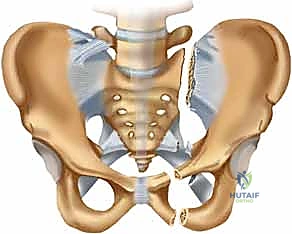

لفهم أهمية التثبيت الخارجي للحوض، يجب أولاً أن نفهم البنية التشريحية المذهلة لهذه المنطقة من الجسم. الحوض ليس عظمة واحدة، بل هو حلقة عظمية قوية تتكون من عدة أجزاء مترابطة بإحكام شديد بواسطة أربطة هي من أقوى الأربطة في جسم الإنسان.

يتكون الحوض بشكل رئيسي من:

* العجز (Sacrum): وهو عظمة مثلثة الشكل تقع في قاعدة العمود الفقري وتشكل الجزء الخلفي من حلقة الحوض.

* العصعص (Coccyx): عظمة صغيرة في نهاية العجز.

* العظمتان اللامسماتان (Innominate bones): وتتكون كل منهما من التحام ثلاث عظام هي: الحرقفة (Ilium)، الإسك (Ischium)، والعانة (Pubis). تلتقي هذه العظام في الأمام عند الارتفاق العاني (Symphysis pubis).